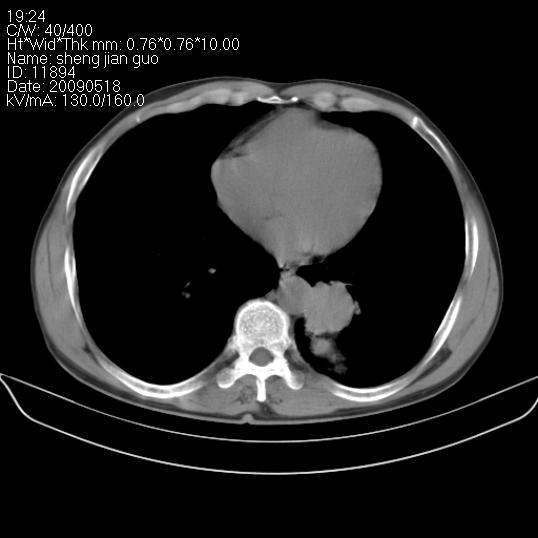

以下是引用zjzjr在2009-5-19 17:25:00的发言:[br]支持楼主考虑,另左肺下叶阻塞性炎症。

以下是引用zhao_bin2008在2009-5-19 17:48:00的发言:[br]支持左肺下叶周围型肺癌并阻塞性肺炎。

以下是引用zsl6918在2009-5-20 7:10:00的发言:[br]左侧中心型肺癌!